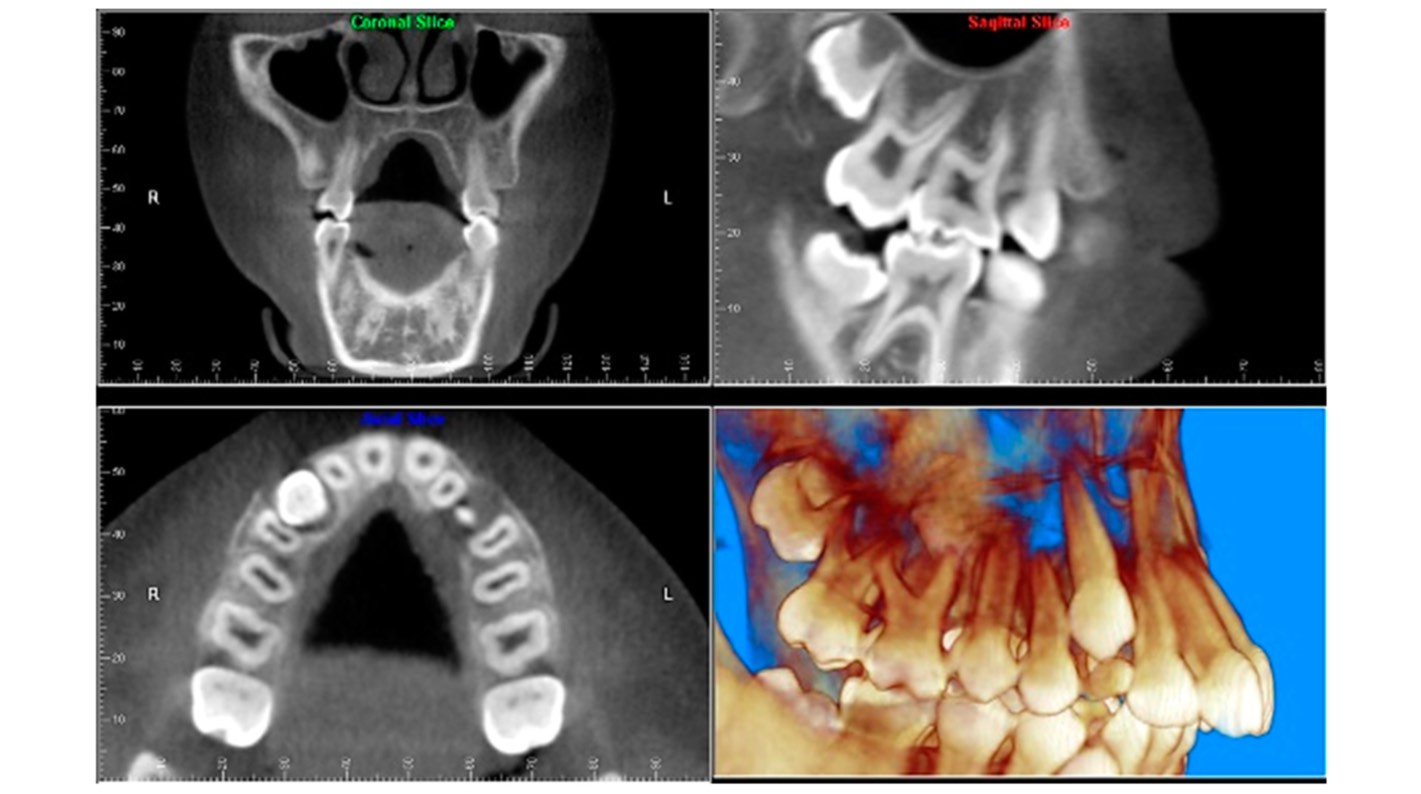

Application du CBCT en médecine dentaire

Si votre domaine de travail est l'endodontie, un scanner CBCT peut fournir une vue axiale, coronale et sagittale que vous ne pouvez pas obtenir avec la radiologie conventionnelle, bien qu'elle soit certainement plus pratique et adaptée aux procédures endodontiques les plus courantes. Le CBCT présente un grand avantage pour éliminer ou réduire le chevauchement des structures, comme par exemple pour la :

Visualisation de l'anatomie des canaux radiculaires : si vous utilisez un scanner CBCT avec un FOV limité, vous pourrez reconnaître les canaux radiculaires avec plus de précision et fournir des mesures plus précises des angulations radiculaires.

Identification de la pathologie périapicale : avec un équipement CBCT, vous aurez une plus grande sensibilité pour établir le diagnostic des lésions périapicales expérimentales. Cependant, il ne faut pas oublier les artéfacts du matériau de restauration qui pourraient entraver le diagnostic.

Identification des fractures de dents : le scanner CBCT surpasse la radiologie conventionnelle dans le diagnostic des fractures dentaires. En effet, à moins d'orienter le faisceau de manière à ce qu'il passe par le plan de la fracture, il n'est pas possible de séparer les fragments dans l'image d'une radiographie intra-orale. Ce diagnostic CBCT peut aussi être altéré par des artefacts.

Analyse du processus de résorption radiculaire interne et externe : avec votre scanner CBCT, vous pouvez non seulement détecter l'emplacement exact, mais aussi déterminer l'étendue de la résorption et la communication avec l'espace du ligament parodontal.